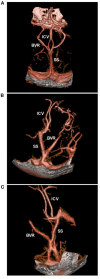

Perimesencephalic nonaneurysmal subarachnoid hemorrhage (PNSAH) is a distinctive disease, representing SAH centered in perimesencephalic cisterns, with negative angiography findings. In recent years, the number of patients with PNSAH has increased significantly; however, the knowledge of PNSAH is insufficient. Therefore, we performed a review of the literature from a PubMed search and recounted our understanding of PNSAH. In this review, we summarized that current high-resolution computed tomography angiography is an acceptable replacement for digital subtraction angiography to rule out aneurysms in PNSAH with strict criteria. The current hypothesis about the etiology of PNSAH is that there is deep vein rupture from aberrant venous anatomy and increased intracranial venous pressure. PNSAH is associated with mild symptoms and lower rates of hydrocephalus and symptomatic vasospasm. For PNSAH, conservative treatment has been the mainstream treatment. PNSAH has a benign clinical course and an excellent prognosis; in long-term follow-up, re-bleeding and death were uncommon.